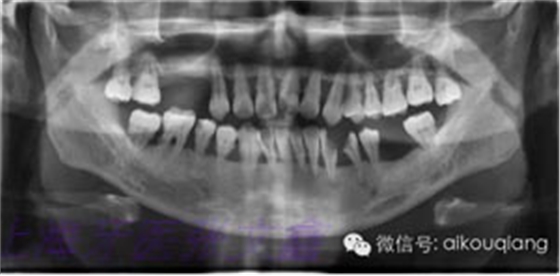

下面這張X光片是比較典型的牙周炎的X光片,該患者全口所有的牙齒都呈現(xiàn)出2~3度的松動(dòng)?;颊攥F(xiàn)在感覺(jué)無(wú)法用牙齒咀嚼。坦白地講,牙周炎發(fā)展到這種程度,很多時(shí)候醫(yī)生也束手無(wú)策了。為了保留更多的牙槽骨,醫(yī)生會(huì)不得不拔掉那些嚴(yán)重松動(dòng)的牙齒。